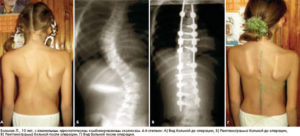

За последние 10-15 лет хирургами различных стран предложен целый ряд металлических конструкций, которые создают внутреннюю корригирующую силу, воздействующую на деформированный позвоночник и удерживающую его в положении коррекции (дистракторы Казьмина, Цивьяна, Шевченко, Фронтино, Гатти, конструкции Роднянского — Гупалова, Двайера и др.). P. Harrington (1949) в дополнение к заднему спондилодезу предложил свой метод внутренней коррекции и фиксации сколиотической деформации позвоночника с помощью дистракционных и компрессионных стержней. В настоящее время в большинстве ортопедических клиник мира данный метод нашел широкое применение и дальнейшее развитие.

В клинике патологии позвоночника ЛНИДОИ им. Г. И. Турнера в течение семи последних лет по методике P. Harrington прооперировано более 400 больных с применением видоизмененного нами инструментария. Полученные благоприятные исходы лечения у большинства наших больных позволяют рекомендовать шире использовать данную методику в практической медицине.